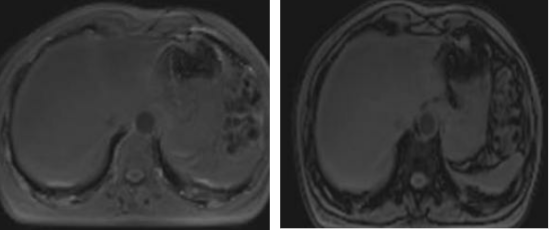

在PDFF图勾画多个感兴趣区测量相应PDFF值以评估脂肪肝程度